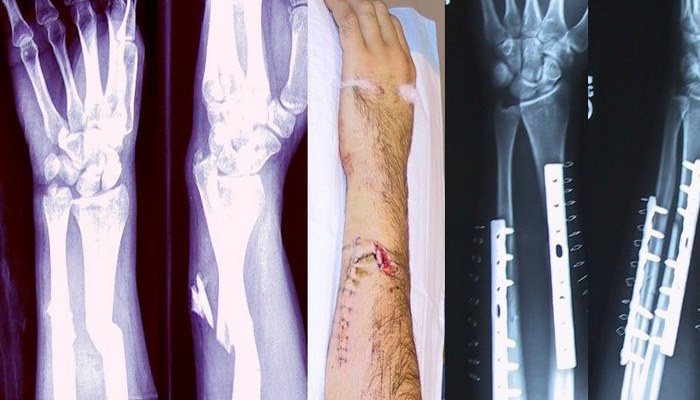

Bone fracture

A bone fracture (sometimes abbreviated FRX or Fx, Fx, or #) is a medical condition in which there is a partial or complete break in the continuity of the bone. In more severe cases, the bone may be broken into several pieces. A bone fracture may be the result of high force impact or stress, or a minimal trauma injury as a result of certain medical conditions that weaken the bones, such as osteoporosis, osteopenia, bone cancer, or osteogenesis imperfecta, where the fracture is then properly termed a pathologic fracture.

Diagnosis

A bone fracture may be diagnosed based on the history given and the physical examination performed. Radiographic imaging often is performed to confirm the diagnosis. Under certain circumstances, radiographic examination of the nearby joints is indicated in order to exclude dislocations and fracture-dislocations. In situations where projectional radiography alone is insufficient, Computed Tomography (CT) or Magnetic Resonance Imaging (MRI) may be indicated.